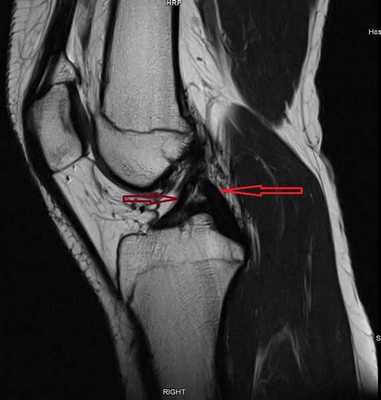

МР-снимок коленного сустава в режиме Т2, контузия кости

МР-изображение субхондрального перелома латерального мыщелка (зона повреждения указана стрелкой)